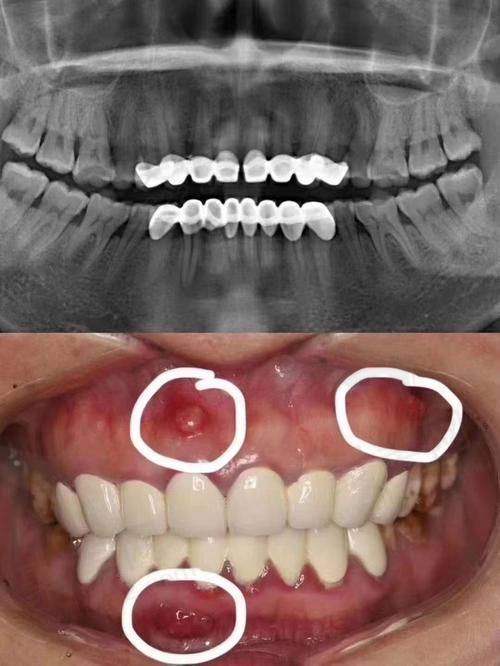

然而,经过几年后,烤瓷牙的问题开始显露出来,导致我每一天都过得郁闷而焦虑。牙龈发炎、腐臭味和不时的隐痛侵扰着我的生活,而医生却告诉我这些都是由于烤瓷牙不当操作引起的。我不禁反思,烤瓷牙是否真的能够改善我的牙齿健康?

医生建议我拆掉这些烤瓷牙,开始进行更为基础的治疗。被欺骗的感觉让我愤怒,我恨那位不负职责的医生。在此之前,我甚至不知道自己的真牙已经遭到腐蚀,到了不得不拔掉的地步。